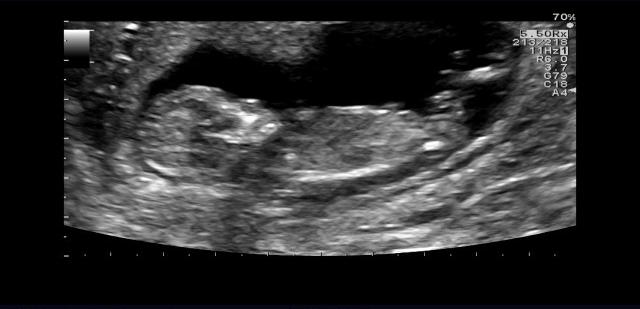

El gobernador de Carolina del Norte ha prometido utilizar su veto para que la norma no se promulgue, pero la mayoría en la Cámara no le permitirá hacerlo. Cooper ha denunciado que esta norma "restringe el acceso sanitario de las mujeres", y ha criticado el texto porque, entre otras cosas, establece la obligatoriedad de hacer tres visitas a una clínica antes de que se permita el aborto. ¿Cuál es el 'problema' de las tres visitas? Pues que en tres ocasiones una madre va a tener que ver esta imagen de su hijo, y claro, cuando lo ves y lo oyes, no abortas, algo que no puede permitirse.